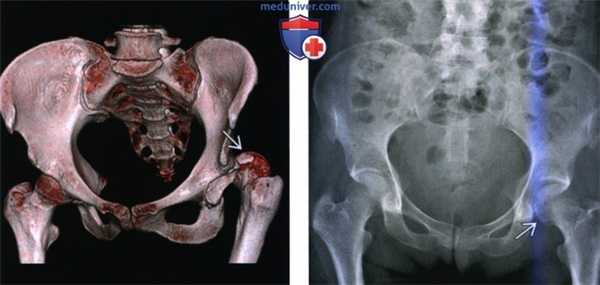

(Слева) КТ в передне-задней проекции, объемная 3D реконструкция: определяется задний вывих головки бедренной кости. КТ выполняется перед закрытой репозицией только если она оказалась неудачной. КТ позволяет оценить положение смещенных осколков, препятствующих репозиции.

(Справа) Рентгенография в передне-задней проекции, выполненная спустя год после заднего вывиха бедра: определяется латеральный подвывих левой головки бедренной кости и нарушение конгруэнтности сустава. Посттравматическая нестабильность бедра является известным, но плохо изученным феноменом.

2. Рентгенография при вывихе бедра:

• Относительный размер головки бедренной кости на изображениях в передне-задней проекции таза служит индикатором направления смещения:

о Отражает относительное расстояние между головкой бедренной кости и приемником изображения

о Задний вывих: головка бедренной кости меньше по сравнению с контрлатеральной стороной

о Передний вывих: головка бедренной кости больше по сравнению с контрлатеральной стороной

• Задний вывих:

о Головка бедренной кости располагается позади, обычно немного кверху от вертлужной впадины

о Внутренняя ротация: большой вертел выделен, малый вертел затенен

о Вывихнутая головка бедренной кости выглядит меньше, чем на контрлатеральной стороне вследствие близости к кассете

• Передний вывих: запирательный:

о Головка бедренной кости расположена медиально и снизу, располагаясь кверху от запирательного отверстия или седалищной кости на изображениях в передне-задней проекции о Бедро согнуто, ротировано кнаружи и отведено

• Передний вывих: подвздошный:

о Головка бедренной кости располагается кверху от вертлужной впадины

о Бедро разогнуто и ротировано кнаружи (малый вертел выделен, большой вертел затенен)

• Передне-задняя проекция диагностическая, проекция Джудета (косая) и боковая-подтверждающие

• Зачастую определяются ассоциированные переломы губы/стенки вертлужной впадины

о Осколок задней стенки обычно треугольный, перекрещивается с головкой бедренной кости в передне-задней проекции

• Переломы головки бедренной кости менее распространены и зачастую плохо визуализируются при рентгенографии